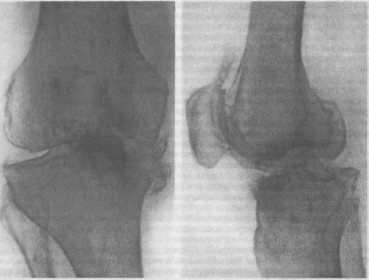

195.

Деформирующий

артроз коленного сустава.

ГОНАРТРОЗ

Причинами

деформирующего артроза коленного

сустава чаще являются посттравматические

и поствоспалительные изменения структур

сустава, нарушающие конгруэнтность

суставных поверхностей. Факторами

риска служат ожирение, плоскостопие,

искривления позвоночника и другие

статические деформации скелета,

нарушающие распределение опорно-двигательных

нагрузок на сустав.

Рентгенологические

признаки:

сужение суставной щели, склероз субхонд-

ральных участков кости, разрастание

краевых остеофитов, кистозное перерож-

274